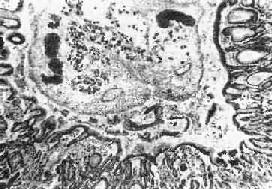

⑵活檢:皮下包塊或結節手術摘除可能發現童 蟲或典型的病理變化

①組織破壞期,蟲體入侵後在腦組織中移行造成隧道狀損傷出血,蟲體停留後破壞腦組織形成穴窟狀病灶,此時周圍腦組織反應尚不明顯;

②肉芽腫或囊腫期,穴窟病變周圍出現炎症反應,組織壞死液化,其內含夏科一 雷登結晶,周圍為肉芽組織及纖維囊壁形成囊腫、肉芽組織,內有大量蟲卵並可找到成蟲。蟲體有遊走的習性,常從囊 腫內遊走到周圍腦組織,形成新囊腫。諸囊腫間有遂道相通,形成多房性囊腫;

③纖維疤痕期,在蟲體死亡或遊走他處 後,囊腫內容物逐漸吸收,蟲卵死亡鈣化,囊壁增厚纖維化。